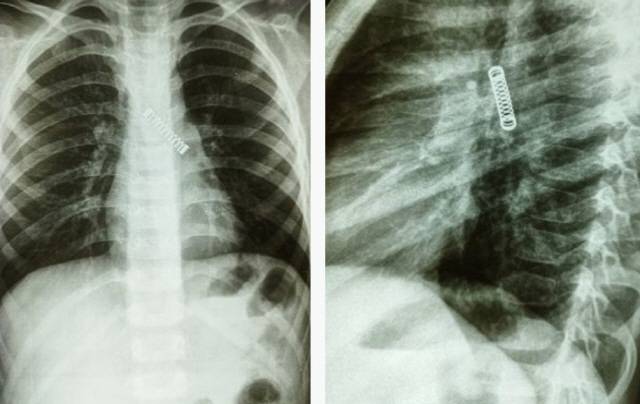

파라과이 5세 남아의 폐에서 3cm 크기 스프링이 발견됐다.

3개월 가까이 기침 증상을 보인 아이는 병원 엑스레이 검사를 통해 뒤늦게 스프링이 박혀있다는 사실을 확인한 것으로 전해졌다.

16일 영국 더선, 더 미러 등에 따르면, 파라과이 국립 호흡기병원 의료진은 지난 8일 5세 남아의 폐에서 금속 스프링을 제거했다. 지난해 12월부터 계속해서 기침을 해온 아이는 원인을 찾기 위해 최근 파라과이 과이라 주 비야리카 병원을 찾았고, 엑스레이 검사에서 왼쪽 폐에 금속 스프링이 박혀있다는 사실을 알게 됐다.

아이는 곧바로 파라과이 국립 호흡기병원으로 이송돼 치료를 받았다. 현재 스프링은 배출된 상태며 아이 역시 안정을 되찾은 것으로 전해졌다. 파라과이 국립 호흡기병원 카를로스 모리니고 박사는 “이물질이 박혀있던 시간 동안 발생한 손상으로 인해 치료 절차가 복잡했다”며 “아이의 폐활량이 감소할 가능성이 있지만, 시간이 지나면서 개선될 것이다”고 말했다.